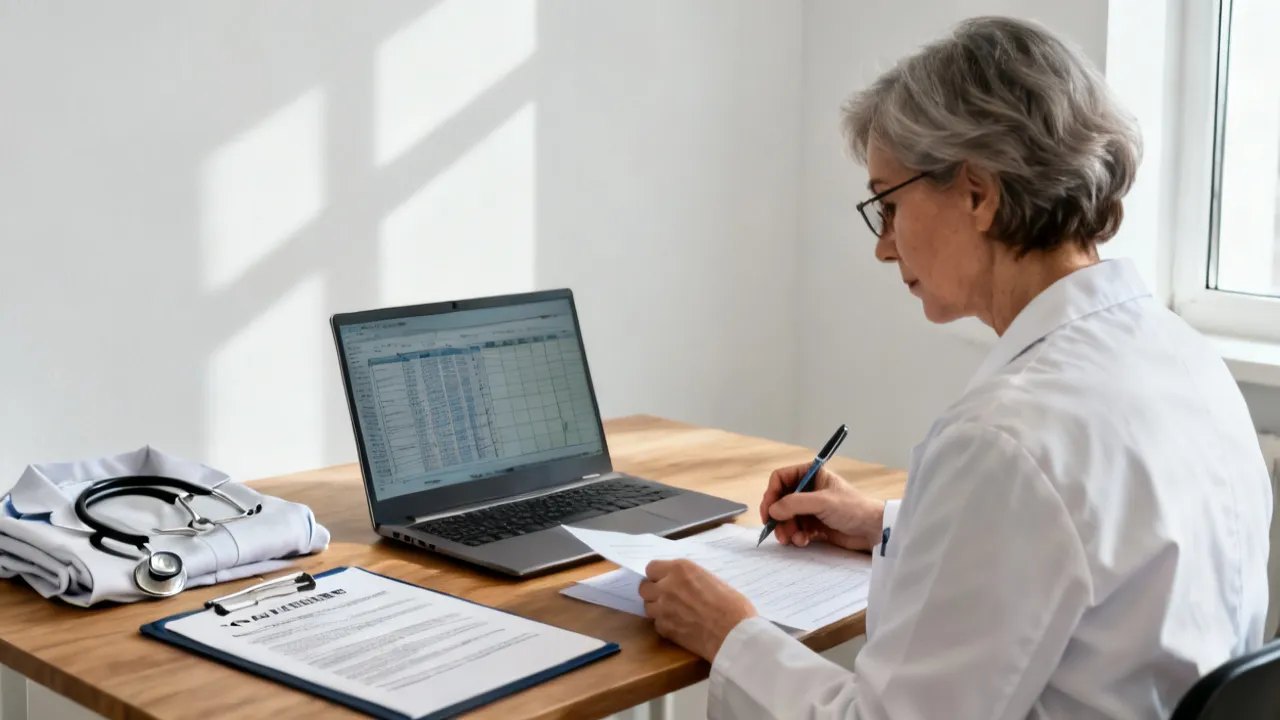

NASH HCC Screening is crucial for early detection and management of liver complications such as non-alcoholic steatohepatitis and hepatocellular carcinoma. Screening helps in identifying individuals at risk before symptoms develop. With advancements in medical technology, screening has become more precise, providing hope for better therapeutic outcomes and patient care in the ongoing battle against liver diseases.

NASH HCC screening plays a crucial role in the early detection of liver cancer associated with Non-Alcoholic Steatohepatitis (NASH). NASH is a severe form of non-alcoholic fatty liver disease that can progress to hepatocellular carcinoma (HCC), a common type of liver cancer. This article provides insights into the importance of screening, methods, and current practices in managing and identifying at-risk individuals for timely intervention.

NASH HCC Screening is a crucial process in the early detection of liver cancer associated with Nonalcoholic Steatohepatitis (NASH). As liver disease has become a growing concern, screening provides valuable insights into patient liver health, aiding in timely treatment strategies. This article delves into the significance, procedures, and advancements in NASH HCC Screening, providing a comprehensive guide from an expert's perspective.

Understanding the implications of Nash Hcc Screening is crucial in medical diagnostics, particularly for liver-related health issues. With advancements in medical technology, Nash Hcc Screening has emerged as a pivotal procedure in identifying and managing conditions affecting liver health, notably Nonalcoholic Steatohepatitis (NASH) and Hepatocellular Carcinoma (HCC). This comprehensive article delves into the significance, process, and advancements in Nash Hcc Screening, offering insights from medical experts on its role in predictive diagnostics and patient management.

Analyzing the significance of Nash Hcc Screening, this article explores its role in early detection of liver complications. "Nash", or Nonalcoholic Steatohepatitis, leads to cancer if unchecked. Early screening is key for prevention. The article offers expert insights on screening processes, benefits, challenges, and potential technological advancements in the field.